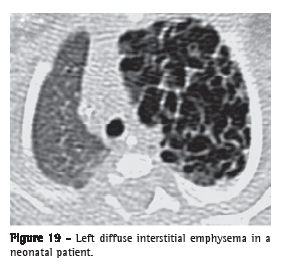

Interstitial emphysema (enfisema intersticial)

Interstitial emphysema is characterized by the air dissection of the pulmonary interstitium, typically located on the bronchovascular sheaths, interlobular septa and visceral pleura; it is more frequently identified in neonates receiving mechanical ventilation (Figure 19). Interstitial emphysema is seldom recognized radiographically in adults and is rarely seen on CT scans. The process appears as areas of air density with perivascular distribution, peribronchovascular distribution or distributed along the interlobular septa (Figure 20), or as rounded areas of low attenuation simulating small bullae or cysts (Figures 19 and 20).(40,41)